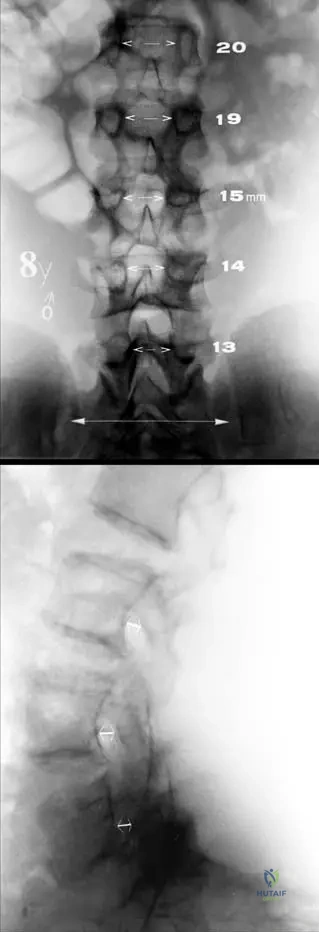

A 5-year-old male with achondroplasia undergoes a lumbar spine radiograph due to persistent back pain. What characteristic radiographic finding is expected regarding the interpediculate distance in the lumbar spine?

Correct Answer: C

Rationale: Fig. 1.14 and its description state: "The interpediculate distance decreases from upper to lower lumbar spine (a)." This is a classic radiographic sign of achondroplasia, contributing to spinal canal narrowing. The normal pattern is for the interpediculate distance to increase or remain relatively constant, making a decrease (A) a key diagnostic feature.

Question 54

View Answer & Explanation

Rationale: Fig. 1.14 and its description state: "Characteristic short pedicles are seen on the lateral view (b)." Short pedicles contribute to the overall narrowing of the spinal canal, which is a significant clinical concern in achondroplasia. Elongated pedicles (A) is the opposite of the expected finding.

A lateral lumbar spine radiograph of a 7-year-old female with achondroplasia is reviewed. What characteristic finding is expected regarding the pedicles?